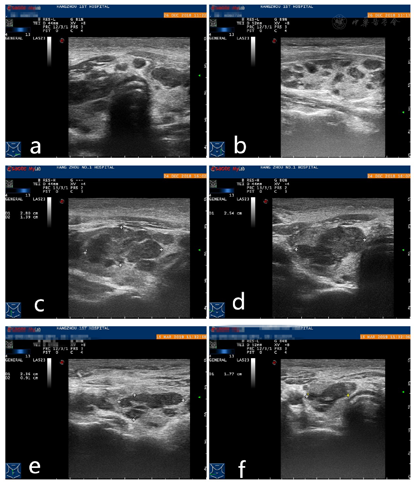

患者,男性,30岁,因"触及颈部无痛性包块1个月"就诊。体格检查:于右颈部可触及3.0 cm×2.0 cm的肿块,质韧,活动度差。浅表超声示:甲状腺双侧叶体积增大,内见多个散在的低回声结节,大者2.8 cm×1.4 cm×2.5 cm,边界光整,外形规则,内部回声欠均匀,彩色多普勒示结节内血流信号不丰富;右侧颈部可见一不均质回声团,大小约4.1 cm×2.9 cm×2.2 cm,边界模糊,外形不规则,CDFI示团块内可见散在条线状血流信号。为明确甲状腺及颈部软组织肿块性质,分别对甲状腺结节及颈部软组织进行粗针穿刺活检:因甲状腺双侧叶多个结节的超声声像图特点类似,故选取了右侧叶其中一个较大结节进行粗针穿刺活检。在超声引导下,用18G100 mm穿刺针各分3次穿入甲状腺右侧叶结节及右颈部软组织肿块,各取得苍白色组织3条。